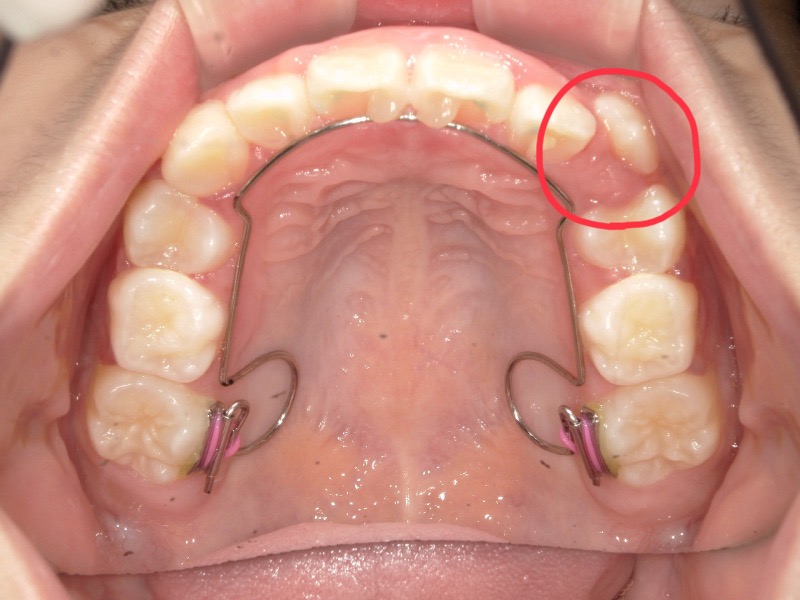

2度目の装置

一度装置は外して様子を見ていたのですがまだスペースが欲しいため再度装置をつけました。

丸で囲っている歯が綺麗に入ることを目的とした装置にもなります。

装置が外れる頃には丸で囲った歯は綺麗に並んでいます。

アクティビティーやマウスピースを継続してくれており卒業も近かったのですが、まだお口が家で開いていることもあり卒業まで少し苦戦していました。